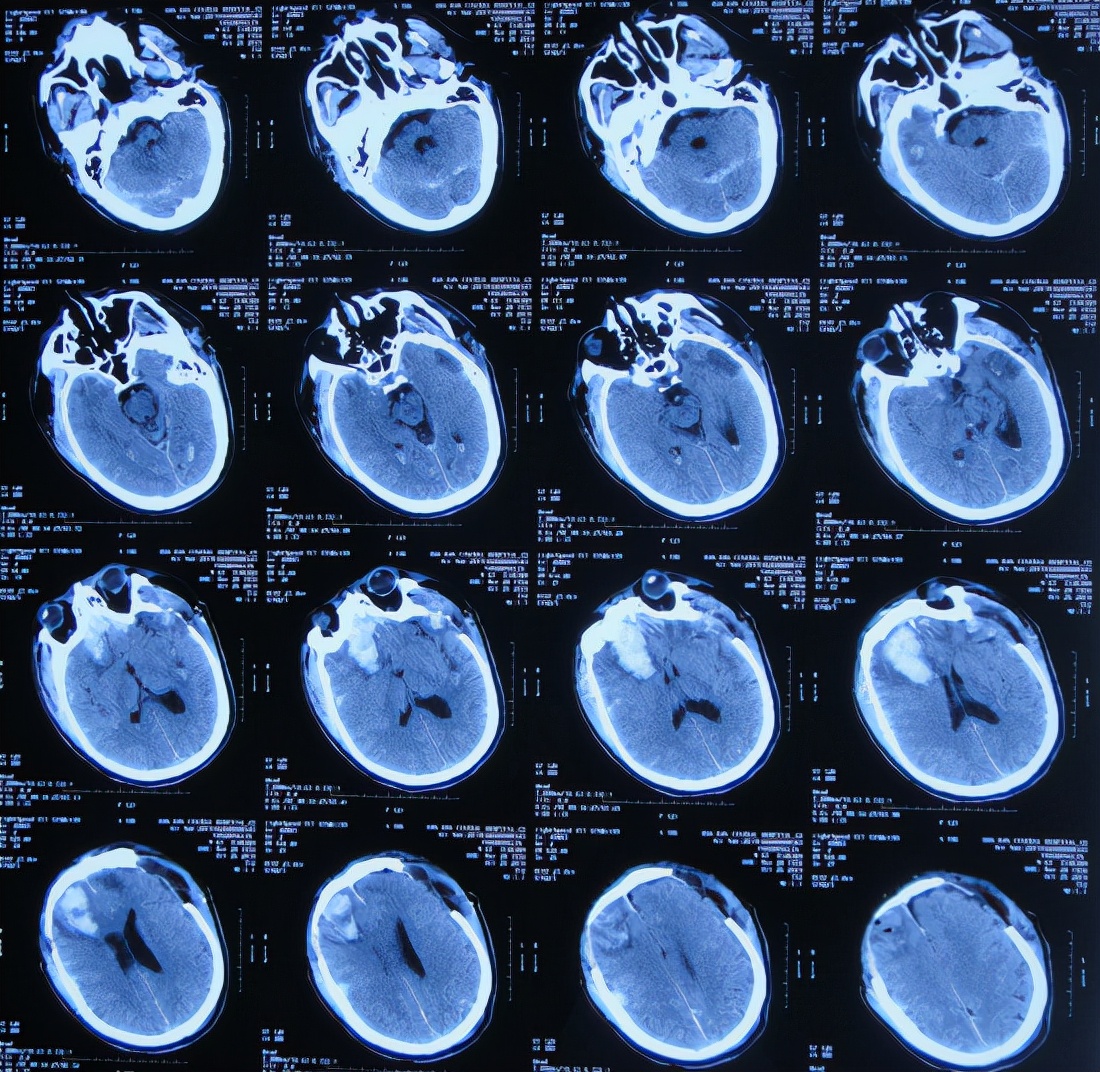

在第3家医院康复治疗近1个月时间内,曾4次查头颅影像(2020年1月22日( 图-24 )、2020年1月29日( 图-25 )、2020年2月10日( 图-26 )、2020年2月19日( 图-27 ))均示脑室仍有扩张,但未给予特殊处理。

图-24: 2020年1月22日头颅核磁

图-25: 2020年1月29日头颅CT

图-26: 2020年2月10日头颅CT

图-27: 2020年2月19日头颅CT

但住院期间间断性发热仅给予药物后仍反复,且大小便时有*禁失**,因此于第3家医院治疗28天后即2020年2月19日,转回当地的第4家河北省邯郸市某三甲医院治疗。

在第4家医院治疗26天,仍间断性发热、大小便*禁失**加重,住院期间曾2次查头颅CT(2020年2月27日( 图-28 )、2020年3月12日( 图-29 ))示脑室仍扩张。

图-28: 2020年2月27日头颅CT

图-29: 2020年3月12日头颅CT